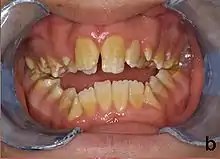

| Amelogenesis imperfecta, hypoplastic type. Note the association of pitted enamel and open bite. | |

People with amelogenesis imperfecta may have teeth with abnormal color: yellow, brown or grey; this disorder can affect any number of teeth of both dentitions. Enamel hypoplasia manifests in a variety of ways depending on the type of AI an individual has (see below), with pitting and plane-form defects common.[4] The teeth have a higher risk for dental cavities and are hypersensitive to temperature changes as well as rapid attrition, excessive calculus deposition, and gingival hyperplasia.[5] The earliest known case of AI is in an extinct hominid species called Paranthropus robustus, with over a third of individuals displaying this condition.[6]

- Enamel has a variation in appearance, with mixed features from Type 1 and Type 2 AI. All Type 4 AI has taurodontism in common. Condition is of autosomal dominant pattern. Other common features may include an anterior open bite,[20] taurodontism, sensitivity of teeth.